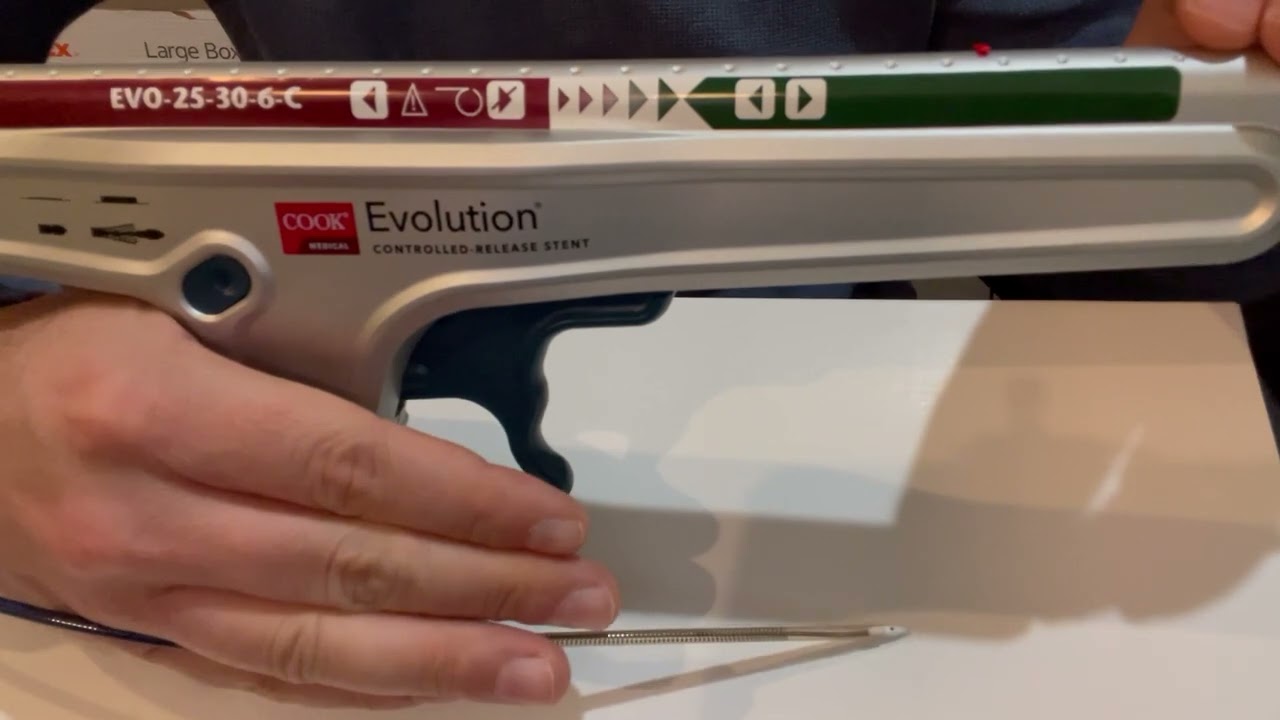

DocWire News recently caught up with distinguished interventional cardiologist Peter Block, MD, at the American Heart ...